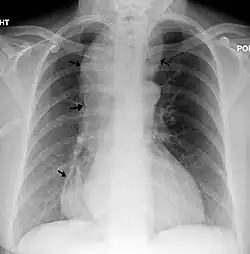

Achalázie (lat: Achalasia) je vzácné onemocnění, při kterém dochází k poruše hybnosti jícnu. Při nedostatečnému uvolnění svalstva na přechodu jícnu a žaludku je jícen neschopen přenášet sousto do žaludku.